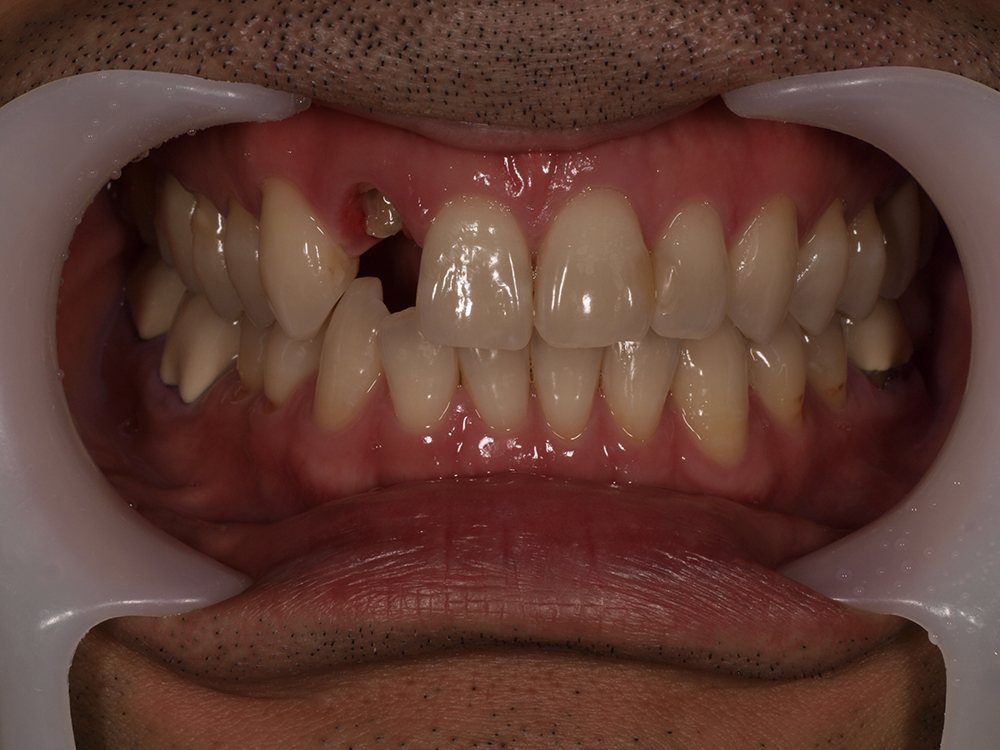

45歳 男性 医療関係者紹介

- 主訴

- 右前歯が取れた(右上2)

- 処置内容

-

1本インプラント埋入+再生療法

抜歯即時埋入⇒抜歯を行い、同時にインプラント埋入(即時埋入)

- 治療費用

- 上顎:約40万円(税込)

- 治療期間

- 約11か月

- リスク

- 上部構造物、仮歯の破折、術後の腫れ(3日)、人工歯根脱落リスクがあります